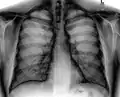

صورة أشعة صدرية تظهر جهاز تنظيم ضربات القلب بلون أبيض(عتامة) في الجزء العلوي من الصدر الأيسر.